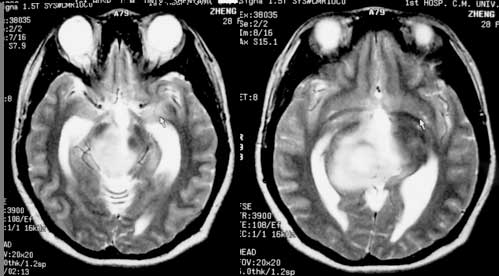

女性,28岁。头痛请会诊

右侧丘脑类圆形等t1,长t2病灶,t1增强明显强化。

女性,28岁。头痛请会诊。

考虑:①丘脑胶质瘤可能大。②脑积水。

t1等信号内出现点状高信号,考虑为出血灶,肿块内侧可见弧形低信号,为脑积液影。长t2,其内有混杂信号,周壁强化明显,内不规则强化,生长位置似在右侧丘脑,又似在来源于侧脑室,故脉络丛乳头状瘤不排外。